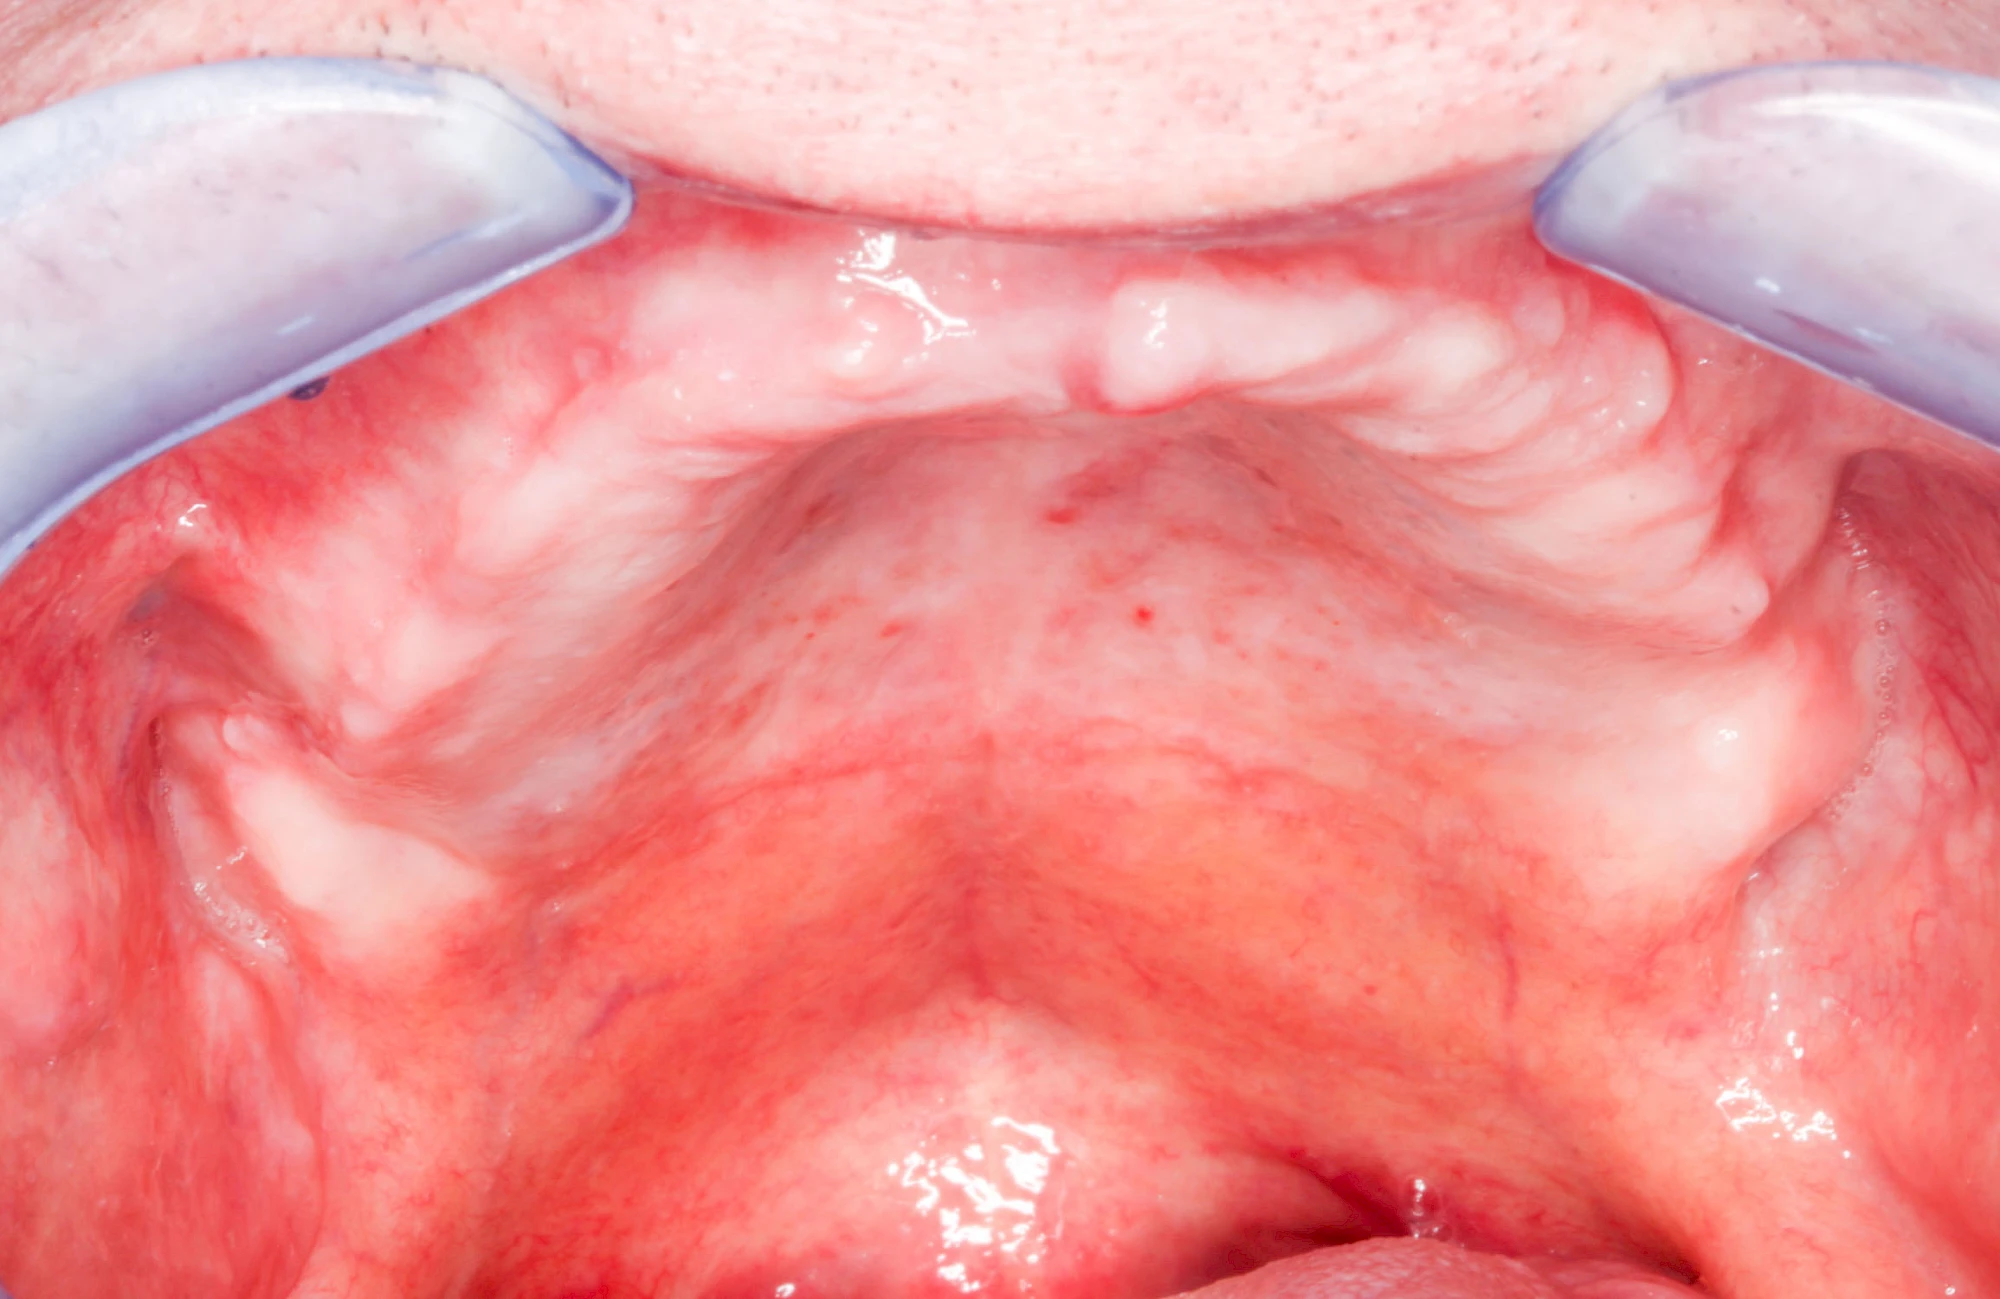

In seltenen Fällen schwindet nur der Knochen, aber nicht die bedeckenden Schleimhäute. In diesen Fällen spricht man von einem sogenannten "Schlotterkamm".

Lippen-Kiefer-Gaumenspalten (LKG-Spalte) sind angeborene Fehlbildungen im Mund-Kiefer-Gesichtsbereich. Die Gewebestrukturen im Bereich des Oberkiefers sind im Zuge der Entwicklungen bis zur Geburt nicht zusammengewachsen. Diese Fehlbildung zählt zu den häufigsten Fehlbildungen des Menschen, von 500 Neugeborenen ist eines betroffen. Die Fehlbildungen können sich auf Lippe, Gaumen und Kiefer allein beschränken, treten häufig aber kombiniert und in seltenen Fällen sogar beidseits auf.

Heute werden in Deutschland Menschen mit Lippen-Kiefer-Gaumenspalten bereits ab Geburt von Experten verschiedener Fachrichtungen (Mund-Kiefer-Gesichtschirurgen, Kieferorthopäden, Logopäden) betreut, damit entsprechende Korrekturen schon frühzeitig erfolgen können. Gerade jedoch bei älteren Menschen ist dies nicht immer geschehen. Diese Menschen tragen häufig technisch aufwendige Zahnprothesen.